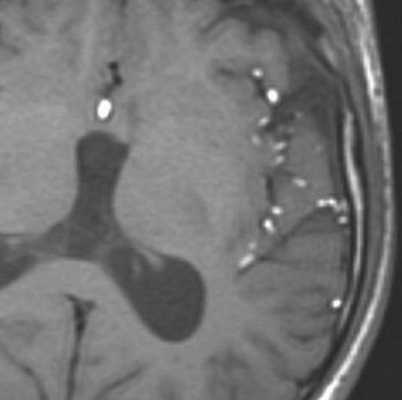

Субтенториальная эпидермоидная киста и арахноидальная киста полюса левой височной доли. КТ, аксиальный срез (а), МРТ, аксиальное Т2-ВИ (b) и аксиальное Т1-ВИ (с) после введения КС. Ни КТ, ни традиционные МР-изображения не позволяют четко дифференцировать эпиде моидные кисты от арахноидальных. Подобно кисте паутинной оболочки, эпидермоидная киста выглядит гиподенсной (а) или гиперинтенсивной (b) и гипоинтенсивной по отношению к паренхиме головного мозга (с) и не накапливает КС (с, стрелка). Однако МР-сигнал в эпидермоидной кисте неоднородный.

Проявления на МРТ схожи с таковыми на КТ; эпидермоиды часто неотличимы от арахноидальных кист или расширенных ликворных пространств на многих последовательностях.

- T1

- обычно изоинтенсивны ликвору

- часто наблюдается более интенсивный сигнал по сравнению с ликвором по периферии образования

- иногда может быть тонкое накопление контраста по периферии